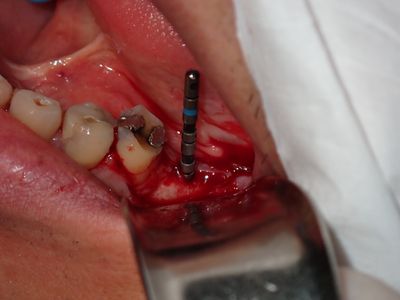

WYu - 36 implant

Loss of lingual bone, osteotomy prepared in ideal position, prepared to about 2.8mm, remainder with combination of densah drills for crestal 1/2 and straumann drills to length. Implant placed with ample bone around it.